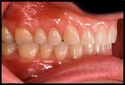

Diş Çekiminden Sonra Kök Kalması Ne Anlama Gelir?Diş çekimi, diş hekimliğinde sıkça başvurulan bir tedavi yöntemidir. Dişin tamamen çıkarılması gerektiğinde, genellikle dişin kök kısmı da dahil olmak üzere dişin tüm bileşenleri çekilir. Ancak bazı durumlarda, dişin kök kısmı çene kemiğinde kalabilir. Bu durum, çeşitli sebeplerle ortaya çıkabilir ve genellikle komplikasyonlar doğurabilir. Bu makalede, diş çekiminden sonra kök kalmasının anlamı, sebepleri, sonuçları ve tedavi yöntemleri detaylı bir şekilde ele alınacaktır. Kök Kalmasının SebepleriDiş çekiminden sonra kök kalmasının birkaç nedeni vardır:

Kök Kalmasının SonuçlarıDiş çekiminden sonra kök kalması, bazı olumsuz sonuçlara yol açabilir: